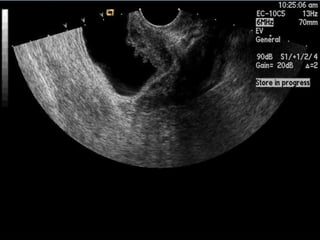

Câncer de Bexiga Estudos de imagens Diagnóstico Ultrassonografia Urografia excretora Estadiamento CT RNM Rx tórax  Cistoscopia + biópsia + biópsias randomizadas

ENDOMETRIOSE VESICAL

Câncer de BexigaEstudos de imagens Diagnóstico Ultrassonografia Urografia excretora Estadiamento CT RNM Rx tórax Cistoscopia + biópsia + biópsias randomizadas